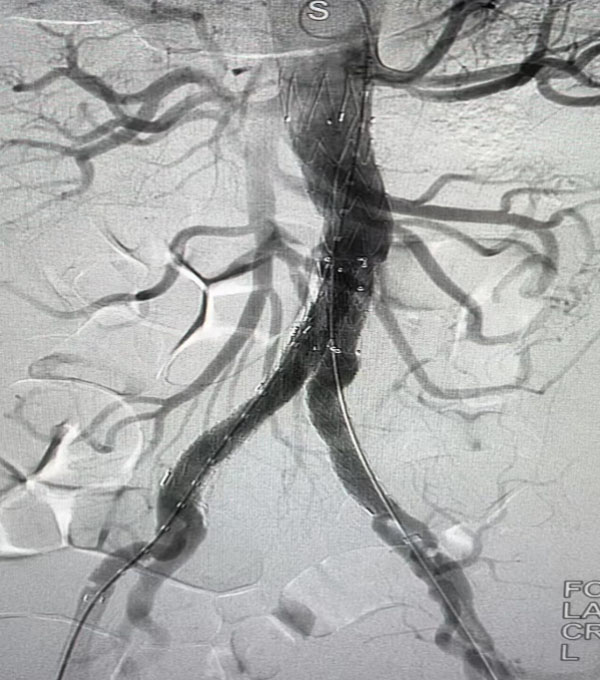

当日上午,待患者麻醉成功后手术演示直播正式开始。在DSA复合手术室,侯五辉主治医师进行病例汇报:患者A型夹层术后8年,远端胸腹夹层动脉瘤形成,拟行腹主动脉置换+内脏去分支+胸腹主动脉腔内隔绝术”。手术由我院心外科负责人赵永波主刀,龚琪副主任医师、要凯主治医师、李超主治医师共同参与,术中夹层动脉瘤与周围组织粘连严重,可能出现大出血危及生命。手术团队运用高超娴熟的技巧,密切配合、攻克难关,顺利完成开放手术腹主动脉置换及腹腔脏器血管重建,随后进行腔内修复手术。该手术充分展现了我院心脏血管外科团队“两栖作战的复合手术能力,得到国内专家一致好评。

腹主动脉腔内隔绝